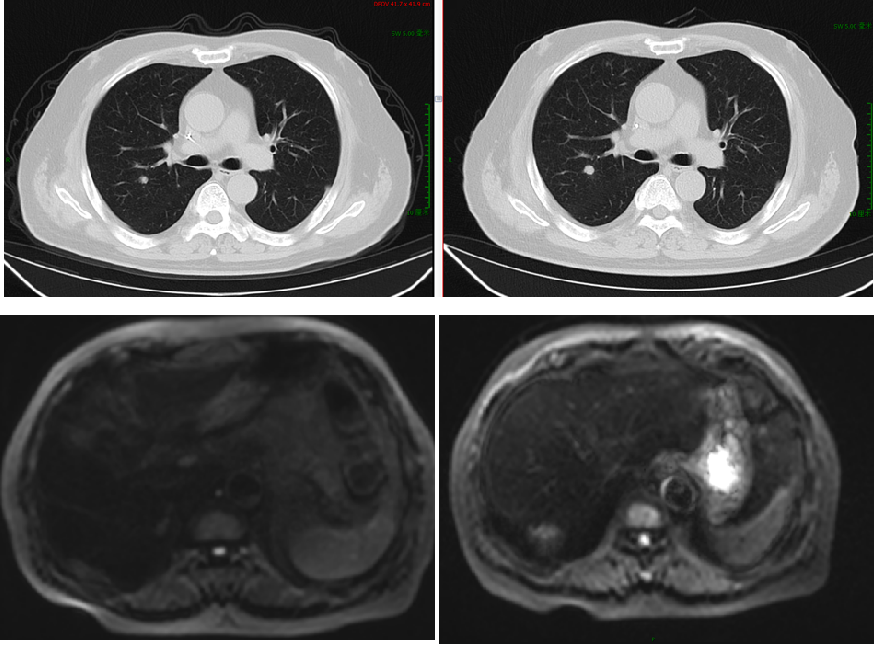

【贝伐珠单抗+雷替曲塞+奥沙利铂】2020-2-11 上腹部MRI增强:“直肠CA根治术+肝转移瘤切除术+胆囊切除术”后改变,与前片(2019-5-9)相仿,肝右叶局部强化欠均,但未见明确的占位性病变。

2020-3-6 胸部CT:两肺多发小斑点灶及微小结节,直径约3-10mm,较前(2019-11-05)部分增大。评估病情PD。

【TAS-102+呋喹替尼】2021-6-11 上腹部MRI提示“直肠CA根治术+肝转移瘤切除术+胆囊切除术”后改变,肝右叶肿瘤介入术后,肝右叶部分病灶较前(2020-12-2)范围缩小,部分病灶较前为新增,肝门区及后腹膜处多发肿大淋巴结,肝右叶见结节、斑片灶,较大者直径约35mm;胸部CT提示右肺上叶斜裂胸膜下结节,较前(2021-2-10)病灶内小空泡消失。两肺多发小斑点灶及小结节,较前部分有所减小,期间有肿瘤标志物进行性升高。

2021-12-7 胸部CT:右肺上叶斜裂胸膜下结节,较前缩小。

腹部MRI:肝右叶部分凝固性坏死边缘伴火星,后腹膜肿大淋巴结。